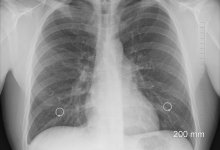

"Я понял, что стал изгоем": как туберкулез меняет жизнь казахстанцев

Люди боятся говорить о заболевании открыто из-за дискриминации.

24 марта отмечается Всемирный День борьбы с туберкулезом. Что нужно знать

Сегодня туберкулез уже не приговор, а заболевание, которое успешно лечится, убеждены врачи.